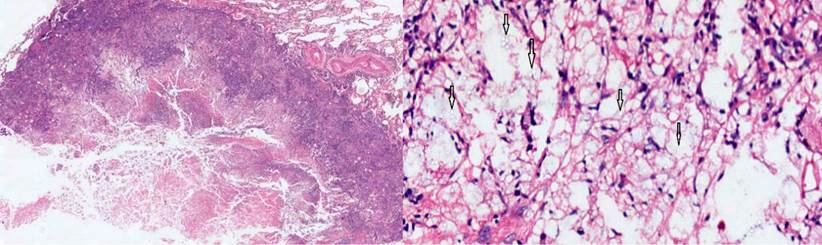

Suspecting tuberculous granuloma, a wedge biopsy of the lower lobe nodule was performed. The pathology report showed lung parenchyma with chronic caseating granulomatous disease, compatible with cryptococcosis, and negative for acid-fast bacilli (AFB) (Figure 3). Fungal cultures confirmed a moderate growth of Cryptococcus neoformans, while negative PPD allowed ruling out latent tuberculosis.

Figura 3 Using hematoxylin-eosin stain, a necrotizing granuloma with debris and histiocytes was observed in the lung parenchyma. Higher magnification (10 X) made it possible to appreciate in detail the cryptococcus spores, indicated with arrows. Source: Own elaboration.